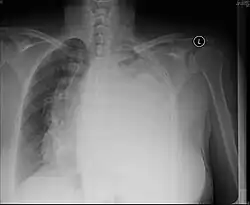

| Left tension pneumothorax with a large, well-demarcated area devoid of lung markings with tracheal deviation and movement of the heart away from the affected side. |

Tension pneumothorax

Tension pneumothorax is an emergent condition in which air gets trapped in the space between the chest wall and the lung. This space is referred to as the pleural space. Because air can't escape from this space, the air pocket grows larger and larger, resulting in the lung collapse closest to the pneumothorax. Forces are transmitted to the mediastinum and effectively "push" the mediastinal structures to the opposite side of the chest.[5]